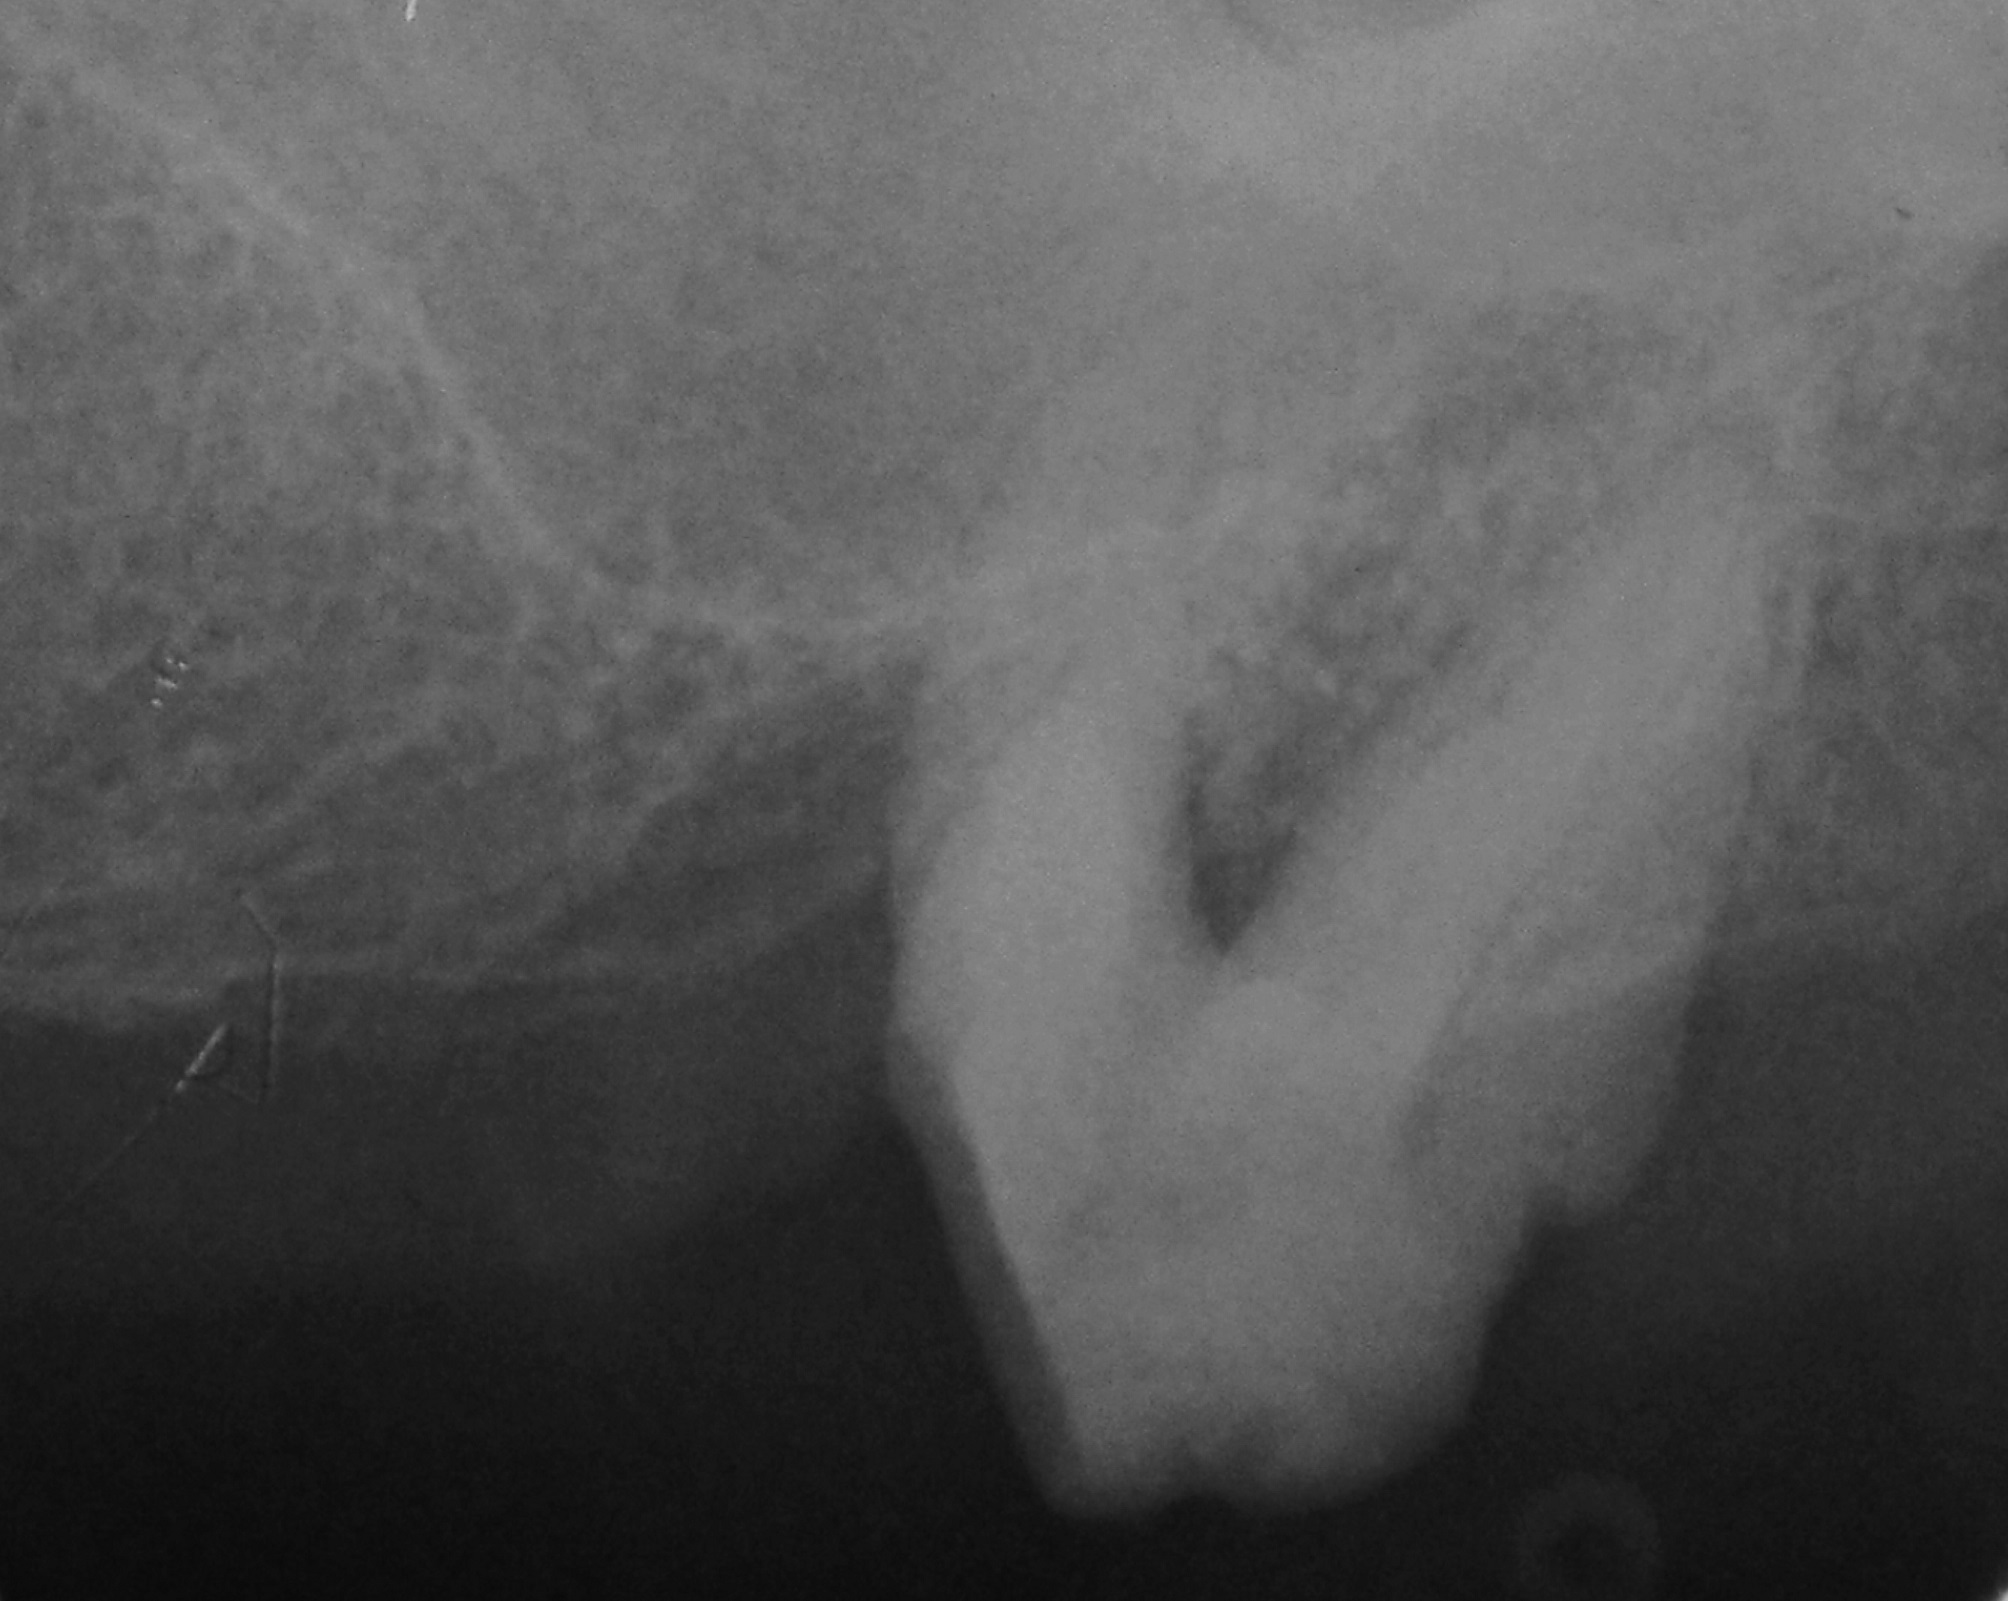

06/06 - Radiograph 5 years post-operative.

Treatment of a periodontal bone defect adjacent to an edentulous site using Straumann® Emdogain® - Prof. Dr. P. Windisch